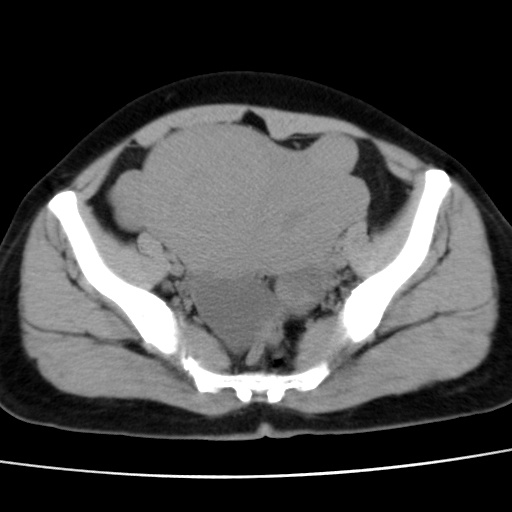

子宫多发肌瘤吗

多发性子宫肌瘤.

考虑多发子宫肌瘤,子宫直肠窝双囊性占位,另直肠周围脂肪密度增高,不知有何病史

支持考虑多发子宫肌瘤~!子宫直肠陷凹积液?

支持考虑多发子宫肌瘤~!子宫直肠陷凹积液!

子宫肌瘤,宫体部后方见液性密度影,是肠道还是子宫与直肠陷窝积液不好说,我觉得它的位置有点高

支持考虑多发子宫肌瘤!子宫直肠陷凹积液!

患者发热,而子宫直肠窝液性灶有明显边缘且局限且囊性,不除外为包裹性积液或脓肿

支持考虑多发子宫肌瘤,子宫直肠陷凹积液可能。

考虑多发子宫肌瘤

1)考虑子宫肌瘤可能性大。2)子宫后方囊性占位性病变,不排除卵巢囊肿可能。

考虑多发子宫肌瘤。子宫后方囊性占位性病变,不排除卵巢囊肿可能。